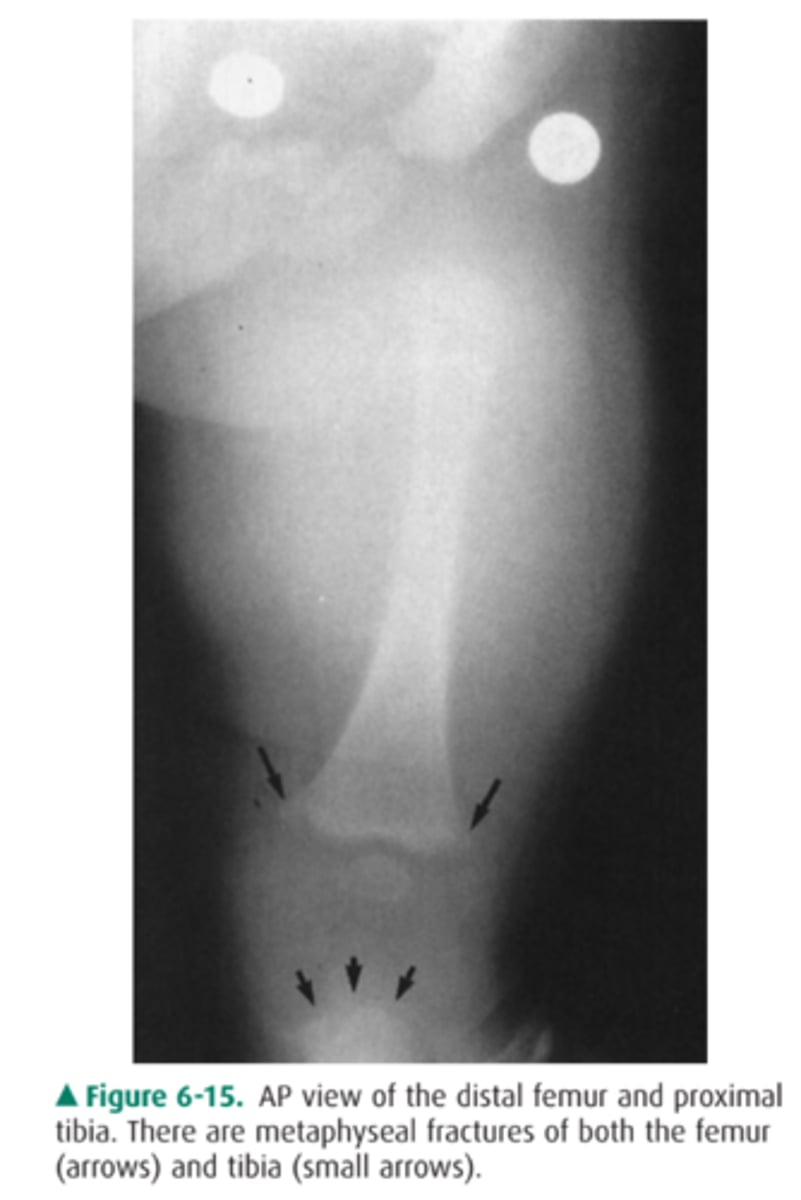

This 5-year-old girl has been limping off and on for 2 months. Her knee is warm and swollen (AP view of the knee).

What is the most likely diagnosis for Case 6-7

(Figure 6-20)?

A. Osteomyelitis

B. A malignant bone tumor

C. A Salter-Harris IV fracture

D. Langerhans cell histiocytosis

Answer

A.

Well defined lytic lesion in the proximal tibia with slcerotic edges. It is extending across the physis to involve portions of both the metaphysis and epiphysis.

Periosteal elevation as seen in 6-11

Nonspecific finding that occurs with local disorders such as fracture, bone tumors, osteomyelitis, and bone infarction.

Hypertrophic osteoarthropathy

Characterized by chronic proliferative periostitis of long bones , clubing of fingers and synovitis, Its asso with Squamou cell carcnimoa and Adenocarcinoma of the lung.